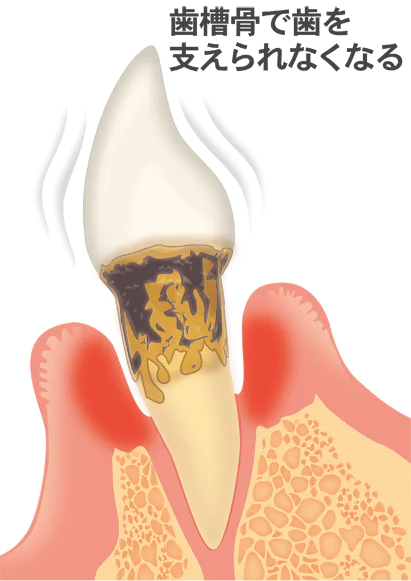

重度歯周病

重度歯周病では、歯槽骨の大きな破壊が見られ、歯根はほとんど支えられず、歯が大きく動揺します。

食事が難しくなり、歯を抜く必要が生じ、入れ歯やインプラント治療も難しくなります。当院では、歯周外科治療や歯周組織再生療法などを行い、なるべく歯を残す治療を行います。